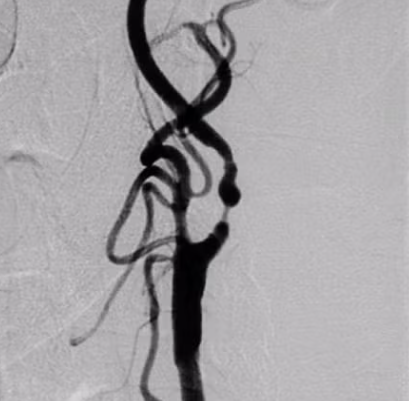

4) 혈관 조영술(DSA)

- 가장 정확한 검사

- 스텐트 시술 시 함께 진행되기도 함

● 3) 경동맥 스텐트 삽입술(CAS)

혈관에 스텐트를 넣어 넓혀주는 시술.